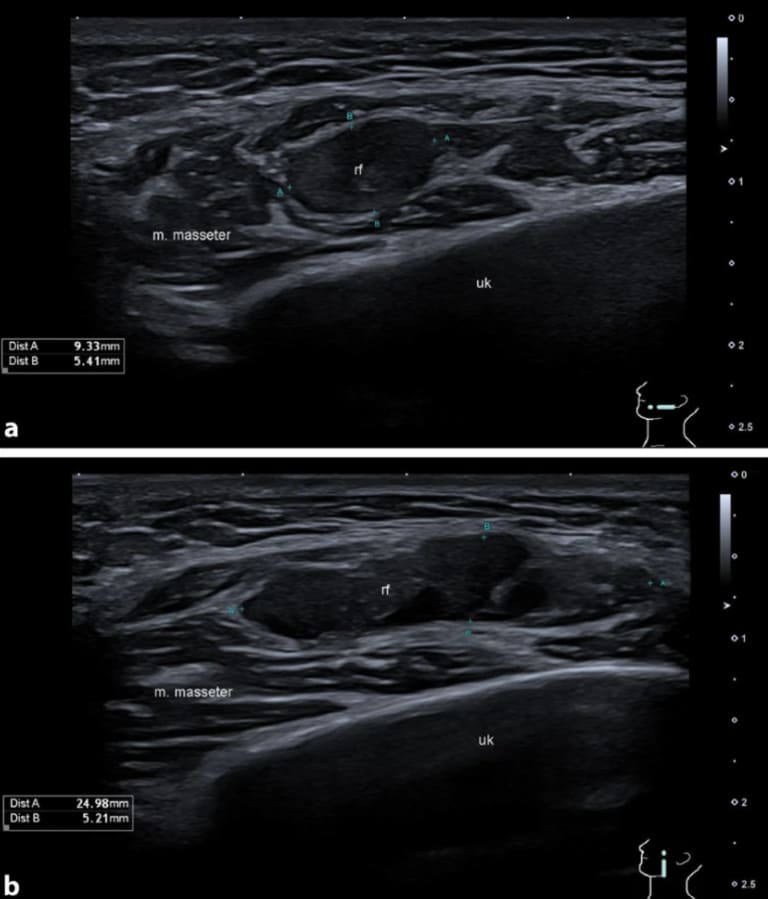

Abb. 2: B‑Bild-Sonographie des Kopfes. a transversal und b longitudinal. rf Raumforderung, uk Unterkiefer, m. masseter M. masseter.